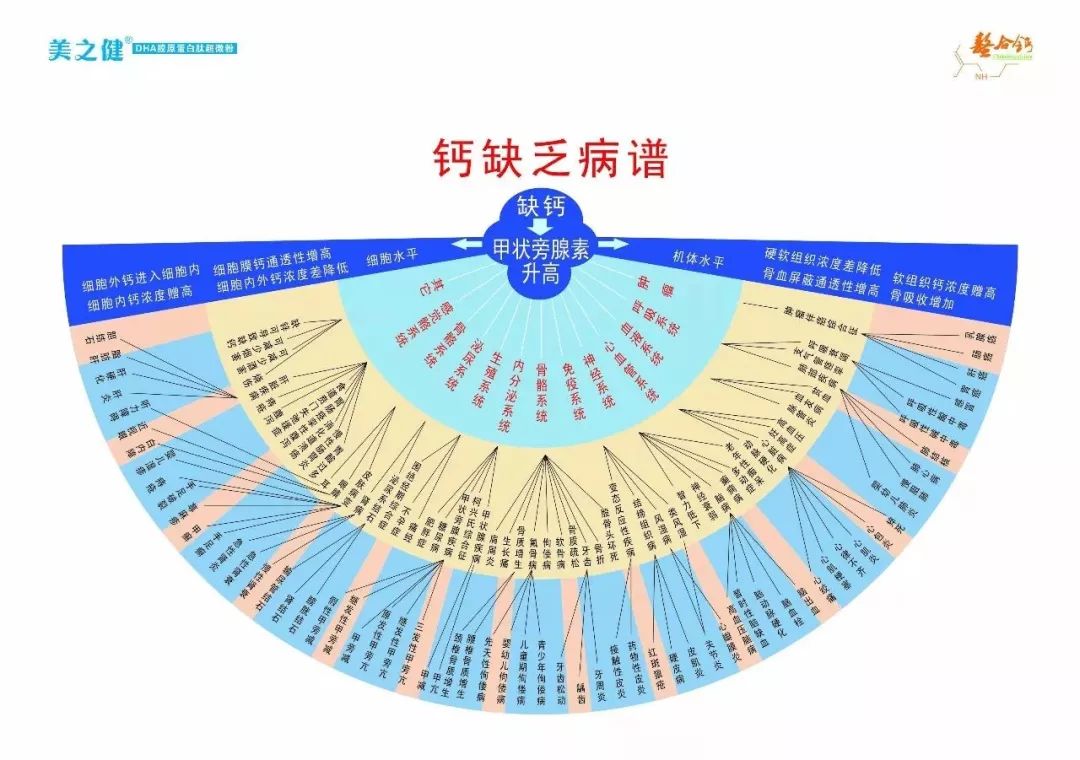

因为饮食结构不合理,吃的东西太好了,造成岁数越大,肾越亏,骨关节反应越强烈,人老骨先老,其实是人老肾先老,反映在骨头上.